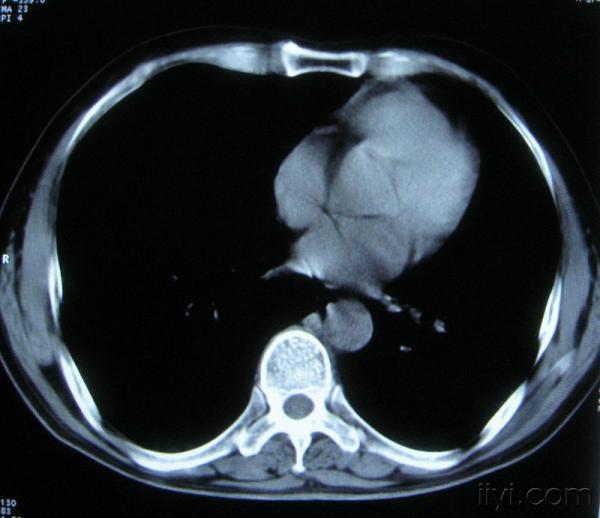

男。60岁,胸片示支气管炎治疗后复查CT。

你指那个肯定是淋巴结,中央系坏死,这很常见,特别在双侧腹股沟会经常看到。这个双侧腋窝及纵隔见多发小淋巴结征。